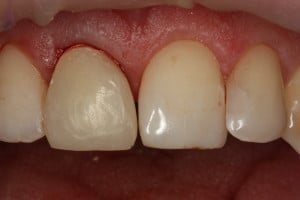

Przykład ekstruzji ortodontycznej za pomocą płytki termoformowalnej i zameczka ortodontycznego: